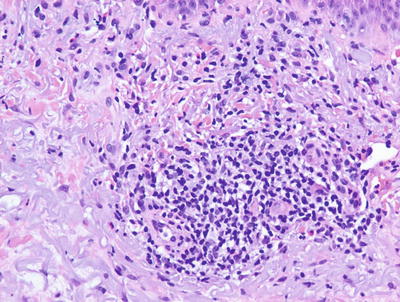

Histologic changes in acute atopic dermatitis are quite subtle. Scant wispy parakeratosis overlies an epidermis that demonstrates slight spongiosis and small collections of Langerhans cells [3] (Fig. 1.2). Scattered eosinophils may be present in the superficial dermis, admixed with increased numbers of lymphocytes [4] (Fig. 1.3). Degranulated mast cells may be present but are rarely observed on routine histologic sections. A folliculocentric pattern with spongiosis concentrated within follicular infundibula has been described, and is more common in darker skinned individuals [5].

Fig. 1.3

A spongiotic dermatitis with scant exocytosis of lymphocytes is seen in atopic dermatitis